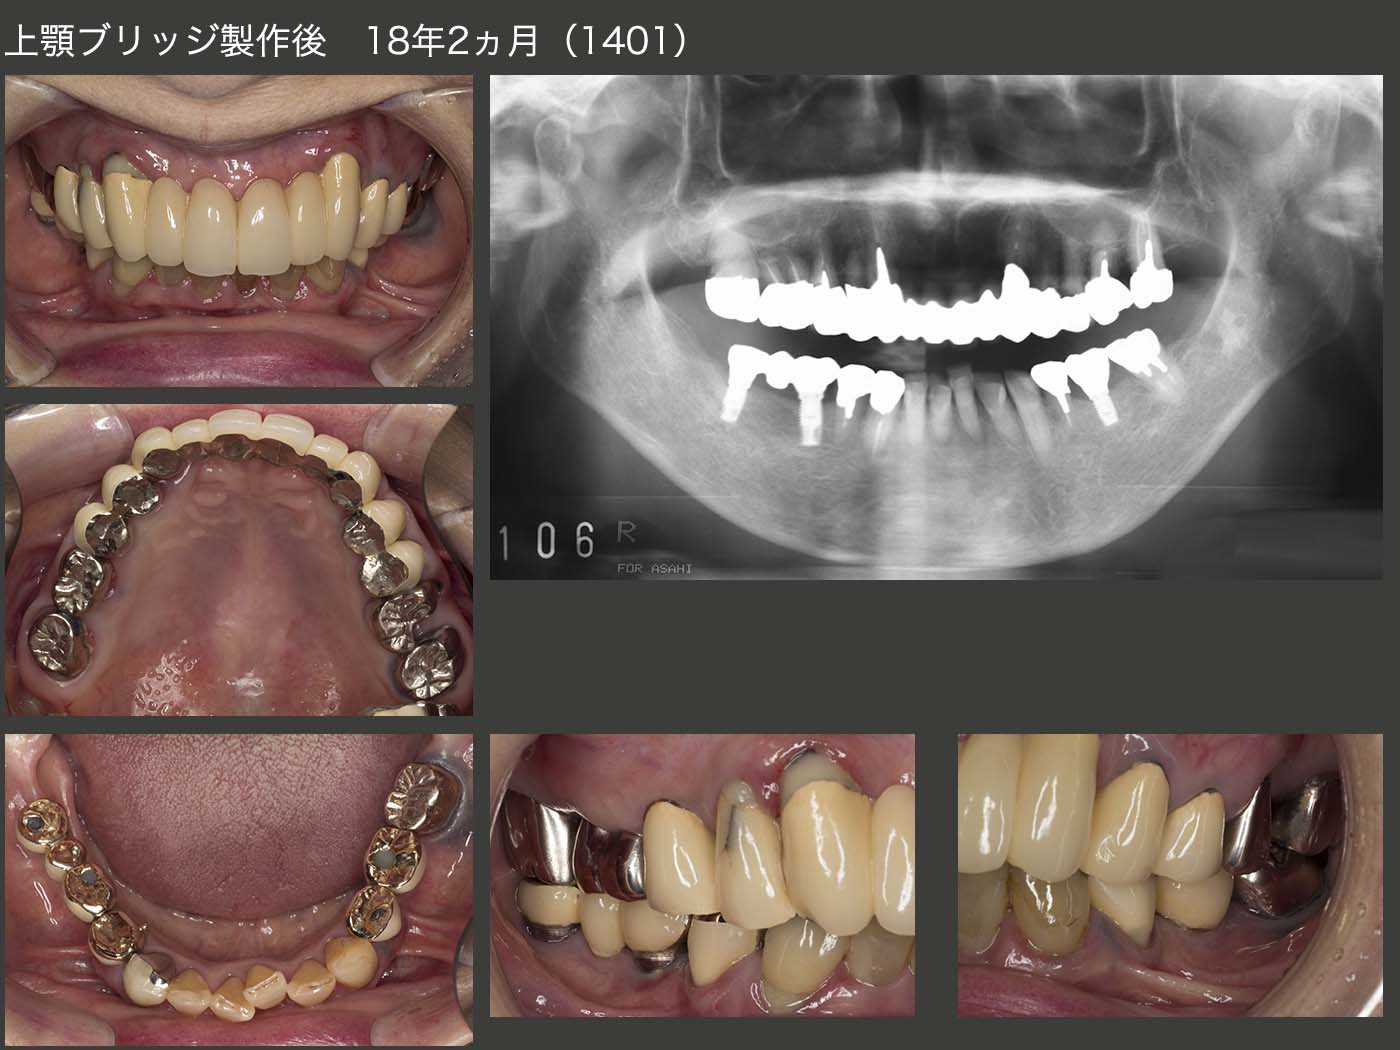

1994年初診,59歳の女性.主訴は下顎の義歯が合わないで,同年新規に製作した.また,95年7月から右上5から左上5のブリッジの新規製作に取りかかり,12月に完成した.スライド下のパノラマX線写真は,94年初診時および98年時の状態.

2014年1月,上顎ブリッジ製作後18年2ヵ月の状態.上顎は,一見問題なさそうであるが,パノラマX線写真から右上4,左上5に明らかなう蝕が認められた.また,右上3,4は,98年にコンポジットレジン修復を行ったが,完全にう蝕を取り除けたかどうか不安であった.このまま放置し,う蝕がさらに進行してしまうと,これらの歯を失う危険があることから,ブリッジの再治療を提案させて頂き,患者さんの承諾を得た.なお,下顎のインプラントは09年に施術した.この頃が私のインプラントの全盛時代であった.

まず,上顎左右3,7を残し,暫間義歯を装着した.ここで義歯に対する反応をみたのち,左右犬歯の冠も除去した.全体に歯肉縁下カリエスが認められたため,歯冠長延長術を施し,歯肉縁上歯質を確保した.

ここで,もう一度固定式のブリッジを装着することが可能であるが,暫間義歯に対する反応がよいことから,可撤式のブリッジ(コーヌス義歯)を選択した.審美性は,メタルボンドのブリッジより見劣りするが,外して清掃できるメリットは著しく大きい.また,将来どこかの歯にトラブルが生じても,補綴装置全体を作り直すことは殆どないと思われる.可撤式ブリッジ装着時の2015年4月の時点では歯肉が赤く,炎症がまだ残っていた.

2021年2月,可撤式ブリッジ装着後5年10ヵ月の状態.歯肉は大分健康になり,歯周ポケットは一番深い所で6mmの値であった.患者さん自身も可撤式ブリッジにして本当に良かったとおっしゃっている.